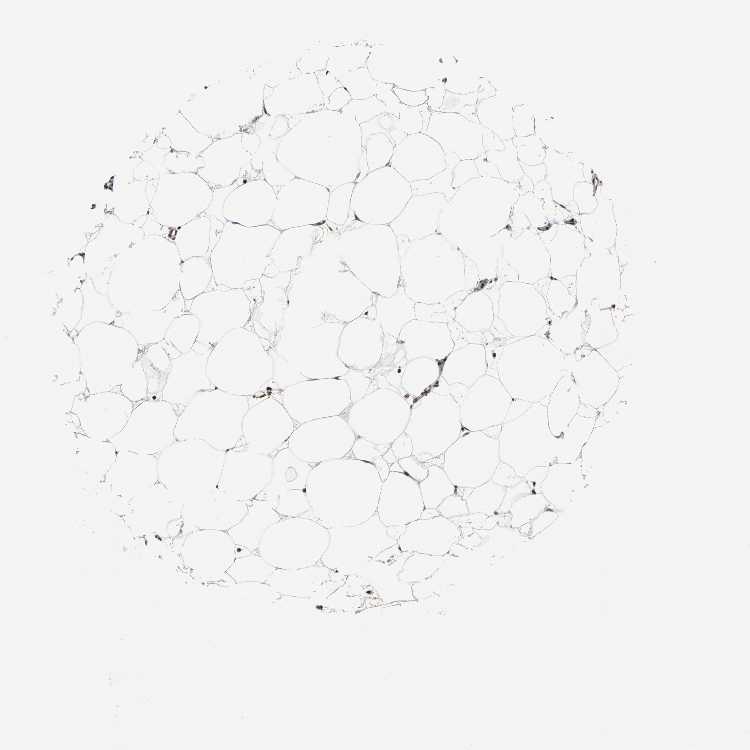

SOFT TISSUE 2 - Antibody stainingi

Antibody staining in the annotated cell types in the current human tissue is reported as not detected, low, medium, or high, based on conventional immunohistochemistry profiling in selected tissues. This score is based on the combination of the staining intensity and fraction of stained cells.

Each image is clickable and will lead to virtual microscopy that enables deeper exploration of all samples and also displays staining intensity scores, fraction scores and subcellular localization as well as patient and tissue information for each sample.

Antibody HPA006628

Fibroblasts Medium

Peripheral nerve Medium